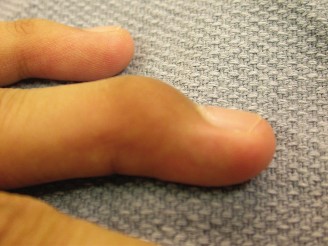

CASE 33 A 64-year-old man presents with the complaint of inability to place his…